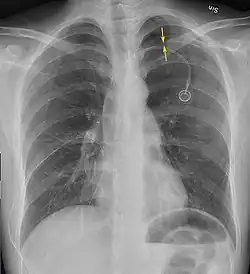

Radiografía

Una radiografía realizada en proyección postero-anterior (de atrás hacia delante) y durante la inspiración máxima constituye la forma de diagnóstico más frecuente.[38] Las imágenes realizadas en espiración, al contrario, no poseen valor diagnóstico significativo,[20] aunque pueden resultar útiles cuando existe una alta sospecha de neumotórax, pero la radiografía en inspiración aparece normal.[39] Si este es el caso, también pueden realizarse radiografías de proyección lateral, aunque esta práctica no se realiza con frecuencia.[20][31]

-

radiografía anteroposterior que muestra un neumotórax de reducido tamaño en el pulmón izquierdo, causado por una punción -

Radiografía lateral en inspiración, que muestra el neumotórax en la parte posterior -

Radiografía anteroposterior en espiración en la que también puede observarse el neumotórax

A veces puede darse una desviación del mediastino hacia el lado contrario en el que se halla el neumotórax debido a las diferencias de presión que crea esta patología. La presencia de esta desviación no implica la existencia de un neumotórax a tensión, que habitualmente se diagnostica a través de signos de gravedad como hipoxia severa y choque obstructivo.[30]

El tamaño del neumotórax (es decir, la cantidad que este ocupa en la cavidad pleural) puede determinarse midiendo la distancia entre la caja torácica y el borde del pulmón. Esto es de relevancia para el tratamiento, ya que los neumotórax de menor tamaño a menudo poseen un enfoque terapéutico distinto. Una distancia de dos centímetros significa que el neumotórax ocupa un 50 % del hemitórax.[20] Las guías de práctica clínica afirman que esta medida debe darse a partir del hilio pulmonar, con un umbral de referencia de dos centímetros para indicar la presencia de un neumotórax de menor o mayor tamaño. La medida también puede realizarse a partir del ápice pulmonar, y en este caso el umbral es de tres centímetros,[40] aunque esta forma de medición puede hacer pensar que el tamaño del neumotórax es mayor si este se encuentra concentrado en la parte superior de la caja torácica.[20][31] Aun teniendo en cuenta esto, estos métodos de medida no poseen una correlación perfecta con el tamaño del neumotórax y, aunque el TAC ofrece imágenes más precisas en este sentido, se desaconseja su uso en estas situaciones clínicas.[20]

No todos los neumotórax son uniformes; algunos ocupan solamente un pequeño espacio en un espacio particular de la cavidad pleural.[20] A veces, pueden hallarse pequeñas cantidades de líquido en la radiografía (hidroneumotórax), que puede estar constituido por sangre (hemoneumotórax).[30] En algunos casos la única manifestación de estos que se da en la radiografía es el signo del surco profundo, por el cual se da un aumento del espacio entre la caja torácica y el diafragma por la presencia de líquido.[35]